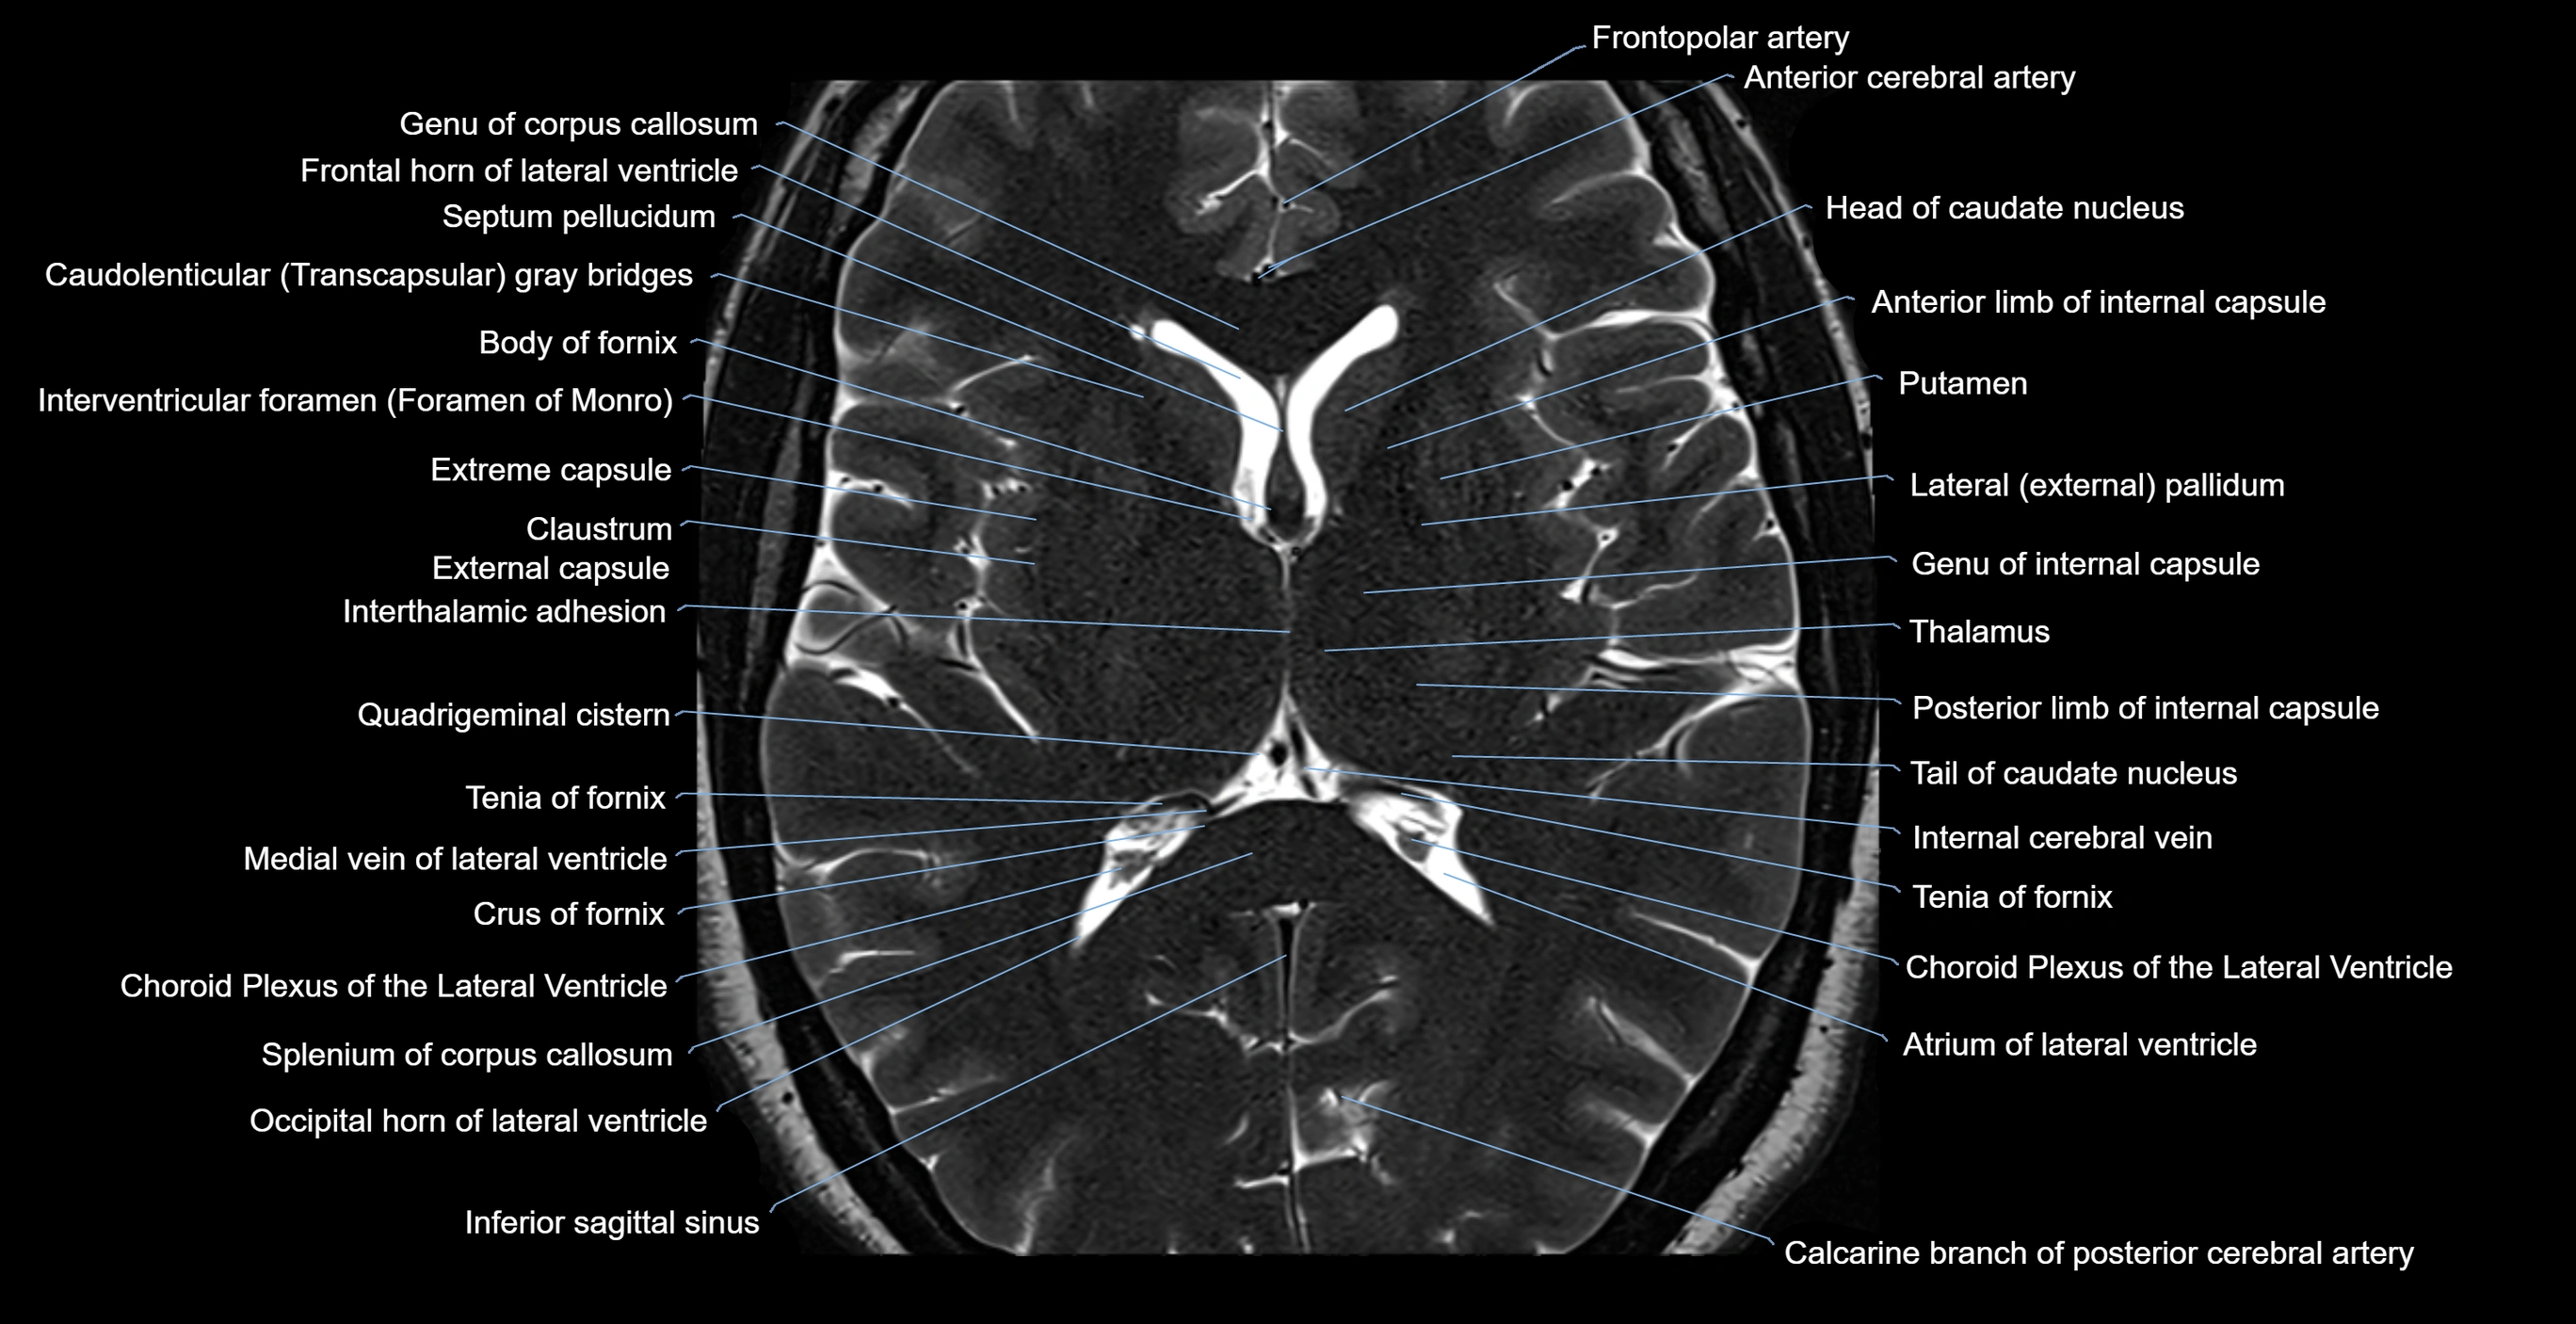

MRI images